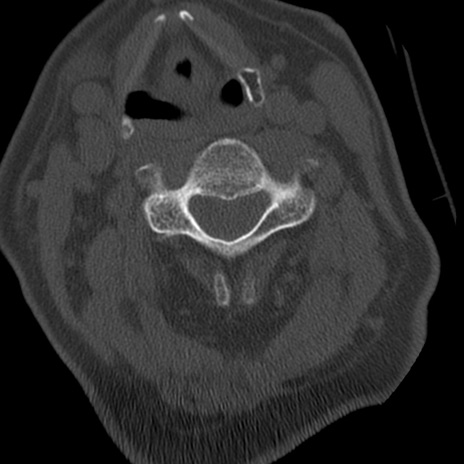

症例50 頚椎CT(横断像)

矢状断像